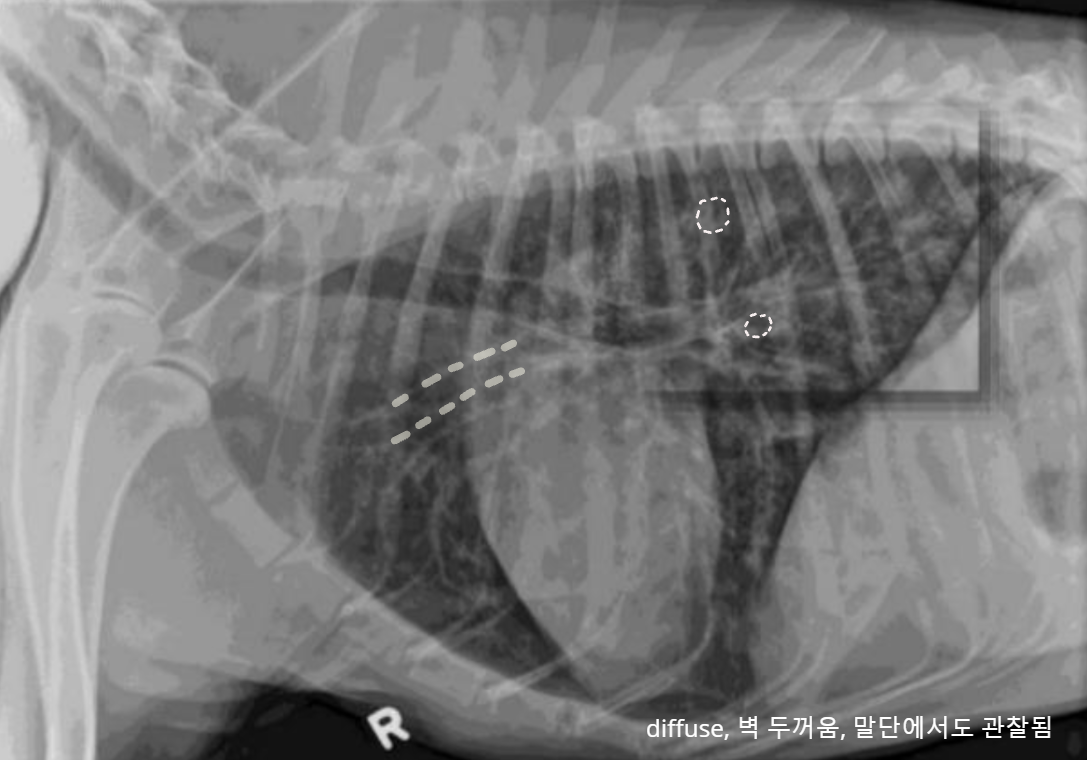

✳️ Bronchial pattern (기관지 패턴)

염증 세포 침윤으로 기관지벽 두꺼워짐

- Doughnut sign : end-on

- Tramline sing : side-on

주의

- 보인다고 해서 무조건 질병은 X

- 말단에서 다수 관찰되면 질병 가능성 ↑